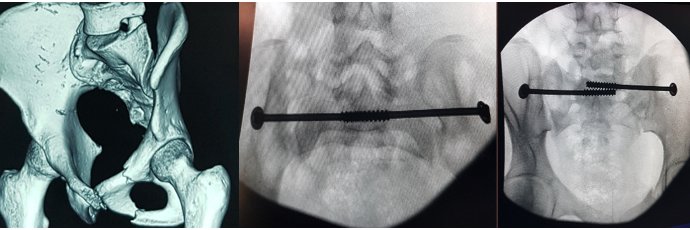

Honoured to attend the launch of the CurvaFix® System — an exciting innovation in pelvic fracture fixatiin

As a pelvic trauma surgeon, it’s inspiring to see technology continue to advance patient care.

#CurvaFix #PelvicTrauma #Orthopaedics